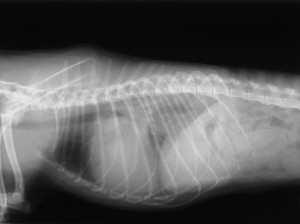

上の子が肺水腫になってしまった時の胸部X線画像です。

心臓はさらに大きくなり、特に心臓のうしろ(画像でいうと心臓の右側)が白く写っています。この部分に水が溜まっているということです。こうなると入院し、酸素室で集中治療を行う必要があります。